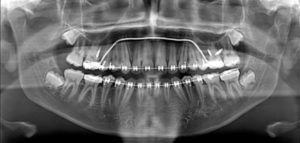

Las imágenes obtenidas mediante CBCT han asumido un papel prominente en el diagnóstico de la disfunción de la articulación temporomandibular (ATM), para la evaluación de